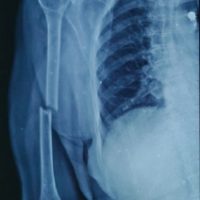

The girls’ mother, likewise, had bilateral, less severe cleft hands and feet, with excellent hand function and shoe-adaptive feet (Fig. 3).

Figure 3: (a) 32-year-old mother of both girls, with bilateral cleft hands; (b) excellent function of both hands; (c) both feet top view; (d) both feet top view; (e) Radiographs of both feet; (f) Cleft palate with hypoplasia of dental enamel; (g) Unilateral cleft lip, sparse eyebrows, and scalp hair; (h) Sparse axillary hair.

Clinical description

Oral examination revealed a unilateral cleft lip and palate on the left side, along with enamel hypoplasia. Her voice had a nasal intonation, indicating velopharyngeal incompetence. Cutaneous examination showed onychodystrophic nail along with sparse axillary and pubic hair, which were vellus in nature. No other congenital anomaly was found on general and systemic examination. Radiographs of both feet showed partial absence of the central 2 rays. USG abdomen and pelvis showed no significant abnormality.

Management

The satisfactory appearance and function of both hands and feet did not warrant any surgical intervention. The clinical findings of cleft lip and palate in the mother, along with ectrodactyly (cleft hands/feet) and ectodermal dysplasia in the form of skin, nail, and hair changes in all individuals, strongly supported the diagnosis of EEC syndrome in the family. A comparison of clinical features of the 3 cases is summarized in Table 1.